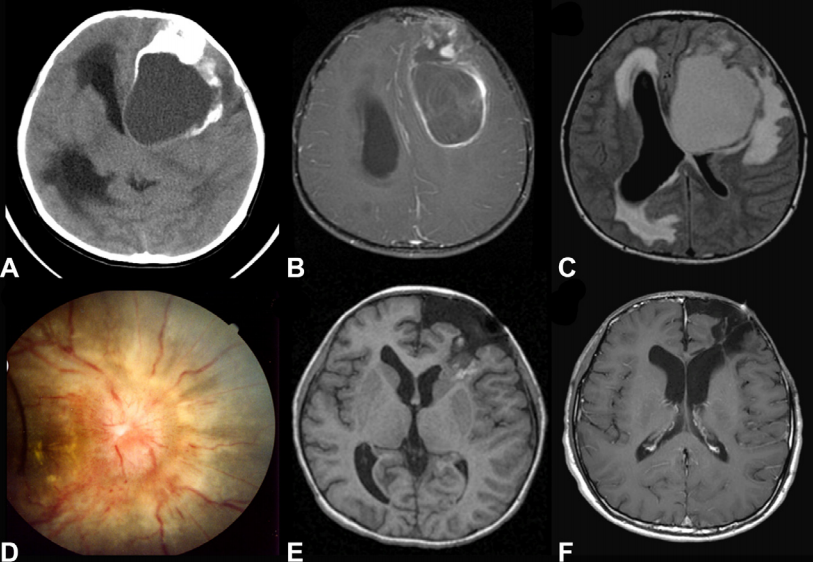

患者是一名10岁男童,症状表现为精神运动迟缓及间歇性呕吐3周。(A) 颅脑CT显示一较大的实性囊性钙化肿瘤,造成的肿块效应和脑积水。(B),肿瘤不均匀,瘤壁边缘强化增强。(C) 磁共振FLAIR)像显示广泛的室周和瘤周水肿。(D)眼底检查图像显示明显的乳头水肿。(E)T1序列显示切除腔底部向侧脑室方向残留肿瘤;组织病理示间变性室管膜瘤。(F)二次切除术,完成大面积的肿瘤切除,然后然后开始进行局灶性放射治疗,较后一次MRI随访无肿瘤复发。